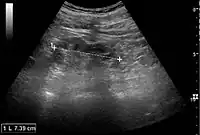

Chronic pyelonephritis with reduced kidney size and focal cortical thinning. Measurement of kidney length on the US image is illustrated by ‘+’ and a dashed line.[20]